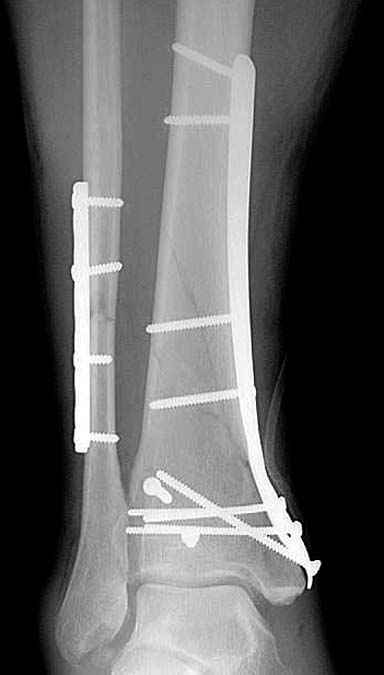

Спасибо за советы. Выполнен МОС обоих костей голени

По представленным послеоперационным снимкам создаётся впечатление сохраняющегося подвывиха + итраоперационно обнаруженный разрыв межкостной мембраны.

Извините за некачественные снимки и неправильную укладку в прямой проэкции. Подвывих рентгенологически не определяется. Кроме этого, после МОС малоберцовой кости интраоперационно однозубым крючком проверена стабильность синдесмоза - он стабилен. Кроме этого, интраоперационно проверена стабильность стопы в голеностопе - люфта ее при боковых отклонениях не определяется, также визуально при этом приеме отклонения малоберцовой кости кнаружи в ДМС не определяется. В дополнение к этому (у ассистента были сомнения) был сделан доступ к межберцовой связке и ее визуальный осмотр- она оказалась целой. При данных обстоятельствах позиционный винт мы не вводим.

Показания для остеосинтеза малоберцовой кости и наружной лодыжки при переломах голени и пилона известны и продолжают обсуждаться, литературу найти можно. Не вдавясь в подробности - в данном конкретном случае остеосинтез наружной лодыжки был желателен для ранней безболезненой реабилитации голеностопного сустава. Надобности в позиционном винте не было и быть не могло. Хочется только надеяться, что проведённая операция была достаточно доброжелательной к мягким тканям, хотя определённые детали послеоперационных Рентгенограмм могут косвенно свидетельствуют об обратном... Так же, как и достигнутая репозиция. Но это не входит в рамки обсуждения, насколько я понимаю. С уважением, Волна